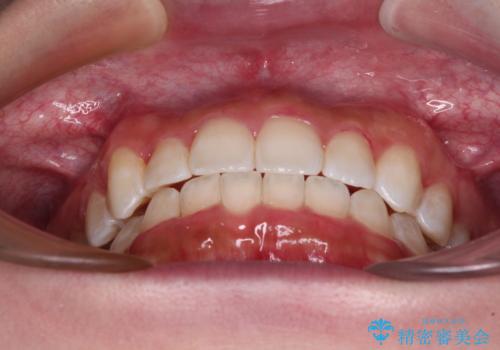

八重歯を改善 目立たないワイヤー装置での矯正治療

前から5番目の乳歯は、後続永久歯である小臼歯と比べて幅径が大きいため、移動に時間がかかりましたが、きれいに仕上げることができました。